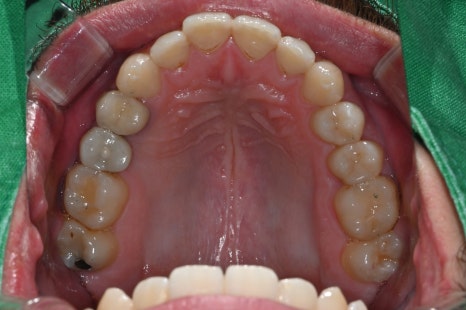

내원 당시 촬영한 위 아래 구강 내 사진입니다.

오른쪽 위 두번째 작은어금니의 상실로 임플란트 치료가 필요한 상태였습니다.

임플란트와 크라운 치료 레진 치료 모두 완료된 후의 구강 상태입니다.

기능과 심미성 모두 만족스럽게 회복되었습니다.